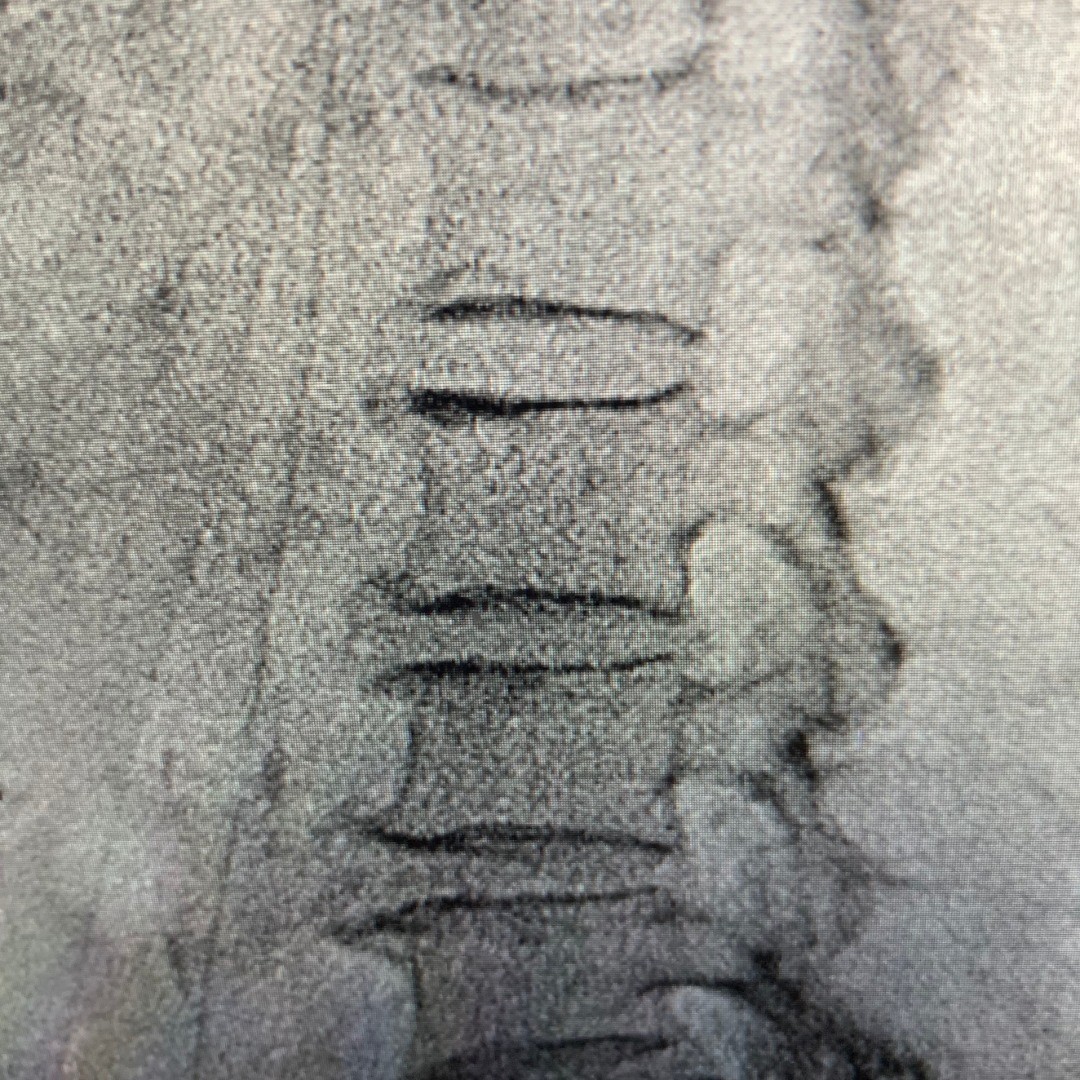

Kyphoplasty is a minimally invasive spine procedure that provides fast pain relief and lifts the fractured vertebral body of the spine; it is used to treat spinal compression factors. Compared to traditional surgery, this procedure uses a smaller incision with fewer complication risks and a faster recovery time.

Kyphoplasty treats unhealed spinal compression fractures that are causing debilitation and chronic back pain.

Osteoporotic spinal compression fractures are especially common in those over the age of 70. Although most candidates for kyphoplasty have vertebral breaks due to osteoporosis, compression fractures can also occur due to cancer or trauma.